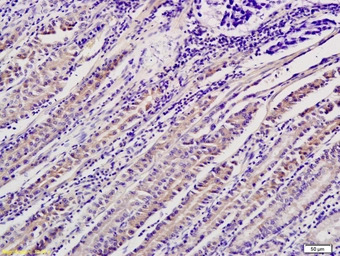

IHC-P analysis of human gastric cancer tissue using GTX51559 ADM2 antibody.

IHC-P analysis of rat small intestine tissue using GTX51559 ADM2 antibody.

Dilution : 1:200